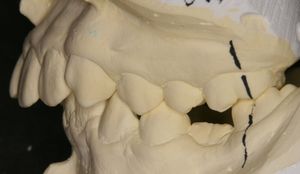

12歳の男の子、前歯がガタガタで出っ歯が気になるので矯正相談に来られました。レントゲン撮影したところ、下顎の第二小臼歯(黄色い丸で囲った部分)が先天的に欠損していて、乳歯がそのまま残っていることが判明しました。両隣りの永久歯に比べて高さが一段低くなっていて、咬み合せに問題があります。このような乳歯はいずれ駄目になって抜歯することになります。今回は、非抜歯矯正を希望されたのでまずはこのままの状態で矯正治療をスタートしました。大学に進学した後に乳歯を抜歯しての再治療を検討するとのことです。